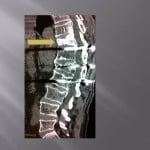

Vertebroplasty in the case of a fracture on posterior material implants

This type of vertebral fracture raises the problem of the entrance way and of the reduced visibility in lateral scopy of the filling of the secondary vertebral at the artrodesis material. The scannographic volume acquisition and the spotting has a large importance to guide the progress of the trocar without being blocked by the arthrodesis screws. The trocar path is outside the screws. An iterative scanner control checks the correct lateral position and the progression in the vertebrae to position at the level of the third anterior and third posterior. The filling is performed in the same way as standard vertebroplasty, the visualization of the cement by continuous lateral scopy is blocked by the osteosynthesis material, for this reason the injection must be done very carefully by alternatively controlling with scanner cuts the correct diffusion of the cement. The scanner control can also be blocked by the artifacts of the osetosynthesis material. Moreover in the cases of osteopenic fractures on arthrodesis, a low density line can exist around the screws showing a potential mobility of the material. In this case, the scanner guide can be very useful to position the tip of the trocar in front of this line. Thus, the vertebroplasty has the additional function to fix the intra vertebral corporeal arthrodesis.

Only the scannographic cuts allow to confirm the correct diffusion around the screws. The clinical results in out series are stackable to the vertebroplasties in the frame of the hyperalgic osteopenic fractures.